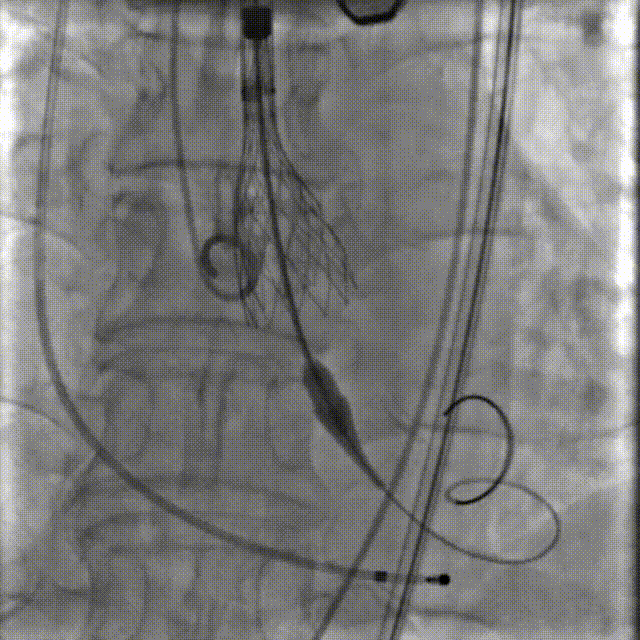

李有金教授 宁夏回族自治区人民医院 “随着人口老龄化加剧,主动脉瓣狭窄患者数量逐年增多,其中高龄、合并多种基础疾病的复杂病例占比不断提升。经导管主动脉瓣置换术(TAVR)作为微创治疗技术,已成为此类患者的重要治疗选择。对于高龄、有恶性肿瘤病史的患者而言,手术的安全性、微创性与长期疗效同等重要,既要最大程度降低手术创伤与并发症风险,也要确保瓣膜的耐用性与患者术后生活质量。 全球首款预装干瓣ProStyle A®的临床应用,为复杂病例治疗提供了全新解决方案。该瓣膜无需术中戊二醛冲洗,大幅缩短了手术操作时间,尤其适合高龄、心功能欠佳的患者。其独特的抗钙化工艺与优化的瓣架设计,既保证了瓣膜的长期耐久性,又能有效规避冠脉风险,为患者的“全生命周期管理”奠定了坚实基础。” 病例简介 现病史:患者半月余前突发抬头时一过性头晕,持续数秒钟,每日发作3-5 次,伴天旋地转感,症状可自行缓解。2025年12月12日就诊于外医院,心脏彩超提示“主动脉瓣狭窄(重度)并关闭不全(轻度),左室壁增厚,升主动脉增宽,左心室收缩功能正常,舒张功能减退”,建议转上级医院诊治。为求进一步治疗,患者就诊我院,门诊以“主动脉瓣狭窄”收住入院。 既往史:胃癌,胃大部切除术后五年。 临床诊断:“1.主动脉瓣狭窄伴有关闭不全(重度狭窄伴轻度关闭不全);2.主动脉瓣钙化;3.肥厚性非梗阻性心肌病;4.心功能不全;心功能III级(NYHA分级);5.升主动脉扩张;6.胃恶性肿瘤个人史” 术前CT评估显示:Type-1型二叶瓣,R-N钙化粘连,瓣叶重度钙化,主要分布在无冠窦瓣叶游离缘、R-N对合缘粘连处及右冠窦基底部;钙化积分933.2mm³;主动脉瓣环直径26mm,LVOT 27.6mm;双侧瓣叶开口高度可,左冠开口高度22.0mm,右冠开口高度20.0mm;主动脉水平夹角57.7°,左室内径偏小;主动脉弓部75.1°锐角弓;外周入路无明显迂曲及钙化,双侧股动脉内径可,右股中分叉。 手术策略 右侧股动脉为主入路,左侧为辅助入路,20F大鞘,股骨头中段穿刺;预装金仕生物 ProStyle A® AV26瓣膜,备29瓣膜,22mm球囊预扩;初始定位对齐瓣环上5mm超高位释放,释放过程中使瓣膜自然下滑至工作位,最终理想位置零位,利用瓣上锚定与封堵,规避冠脉风险;术前适当补液; 手术过程 Step1:主动脉根部造影; 主动脉根部造影 Step2:使用“先瑞达”22mm球囊预扩,无腰无漏,冠脉充盈良好; 球囊预扩 Step3:将ProStyle A®预装干瓣送至目标位置,初始定位后缓慢释放,观察瓣膜自然下滑至理想工作位; 定位 释放至工作位观察 Step5:瓣膜完全释放后,再次造影,显示瓣膜位置、形态良好,导管测平均跨瓣压差由术前60mmHg-降至1mmHg,冠脉血供正常; 最终造影 Step6:术后即刻超声监测,人工瓣膜位置固定,瓣叶启闭无受限,瓣周少量反流。 术后患者病情稳定,已于一周后出院。 结语 作为宁夏回族自治区心血管疾病诊疗的核心高地与区域医疗中心建设的标杆单位,宁夏回族自治区人民医院始终坚守“敬佑生命、救死扶伤”的医者初心,以“技术引领、学科兴院”为发展理念,在心脏大血管领域持续深耕,构建了集“精准评估-个性化方案-微创治疗-全程康复”于一体的诊疗体系。此次西北首例ProStyle A®预装干瓣植入手术的圆满成功,不仅是医院在复杂结构性心脏病介入治疗领域的又一突破性成果,更彰显了医院在引进前沿技术、转化创新器械、服务复杂重症患者方面的责任与担当。 Prostyle A®预装干瓣——助力临床最优化解决方案: 预装干瓣 便捷顺安:金仕生物专利抗钙化技术运用纳米技术去除组织内的细胞碎片和磷脂,封闭游离醛基,从根本上阻断了瓣膜钙化的多项因素,显著提升了瓣膜的耐久性;同时,相比较传统戊二醛保存方式,干式存储最大限度的保留心包的亲水亲油平衡,还原组织天然曲柔性,进一步保障了瓣叶开合,保证长期耐久性; 平衡径向支撑力:Prostyle A®瓣架网孔比例按照病例解剖结构的特殊设计,使瓣膜在狭窄最重的地方良好的撑开,同时避免对瓣环及周边组织的过度压迫,有效降低传导阻滞风险; 精准释放:底部桶状设计更易迅速锚定,协同释放张力小,助力最终精准释放; 过弓柔顺:较细的输送系统直径+亲水涂层,显著提升输送系统通过性,有效减少血管并发症的发生,内连鞘版本最小尺寸等效14F大鞘; 专家简介 李有金 宁夏回族自治区人民医院(点击查看专家详细简历) · END ·